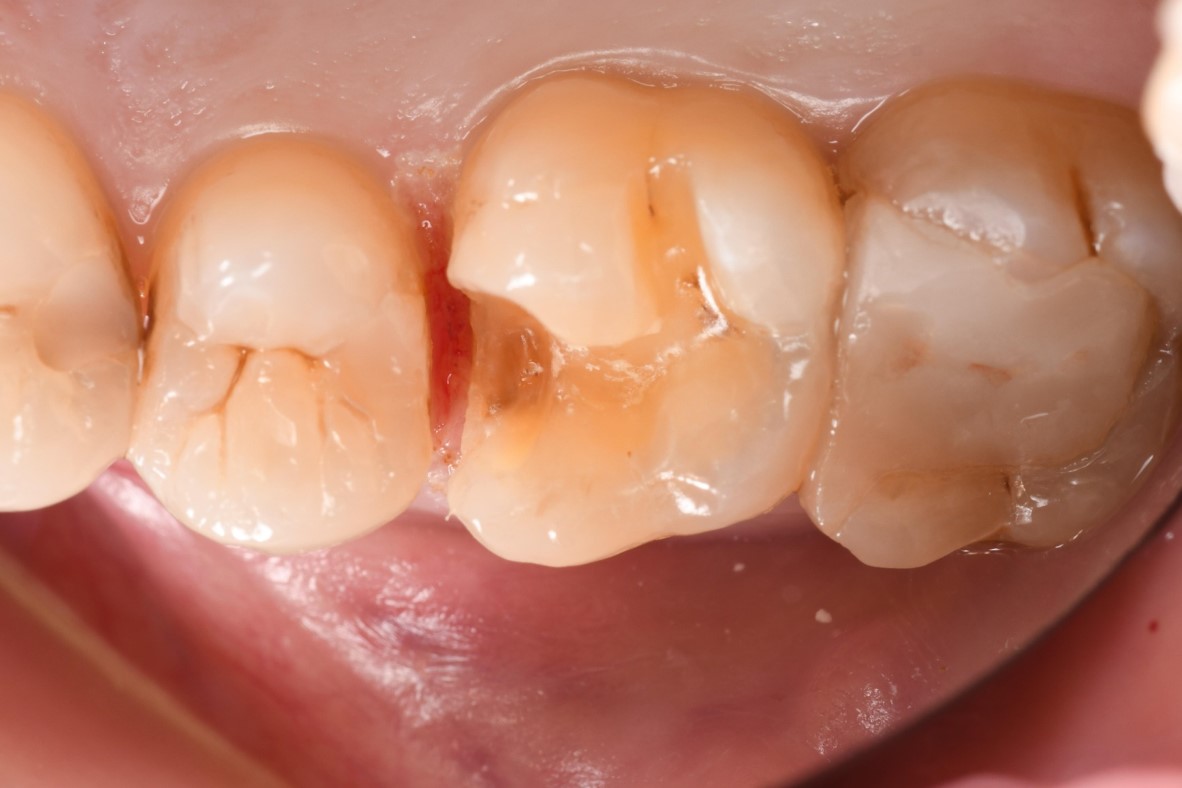

治療前,大臼齒冷熱敏感

瓷塊製備